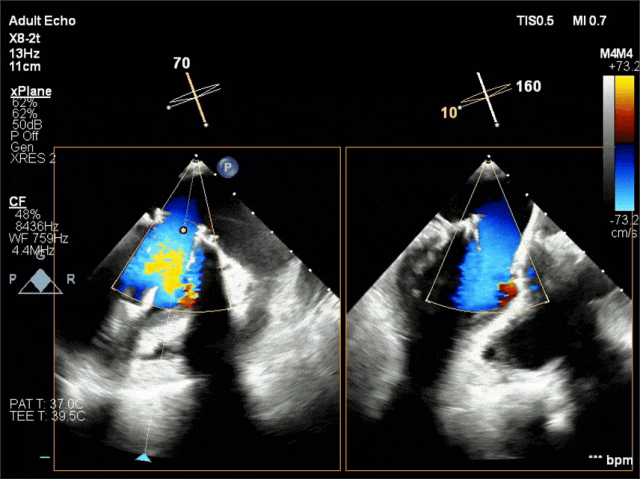

术后超声

二尖瓣瓣口峰值流速1.17m/s,平均跨瓣压差2mmHg,无瓣口反流,无瓣周漏。